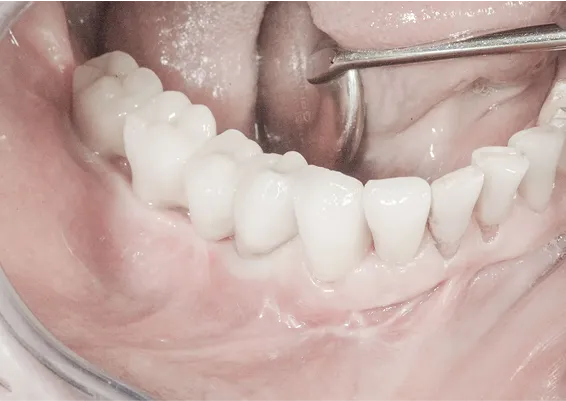

TRÓJWYMIAROWA REKONSTRUKCJA WYROSTKA ZĘBODOŁOWEGO PRZY UŻYCIU INDYWIDUALNIE DRUKOWANYCH SIATEK TYTANOWYCH YXOSS ReOss

To kolejna metoda umożliwiająca precyzyjną odbudowę zadanego kształtu tkanki kostnej przy użyciu standardowych materiałów kościotwórczych, kości własnej lub PRF oraz zewnętrznego rusztowania w postaci siatki z biozgodnego stopu tytanu. Siatka jest indywidualnie projektowana w technologii CAD CAM i następnie drukowana dla konkretnego przypadku.

Dotychczas stosowane stabilizatory zewnętrzne w formie siatek tytanowych używane do regeneracji kostnej lub w zabiegach odtwórczych w chirurgii szczękowo-twarzowej uwzględniały materiały ręcznie doginane i formowane podczas zabiegu operacyjnego. Zastosowanie technologii CAD CAM dla potrzeb druku materiałów przeznaczonych do indywidualnej rekonstrukcji kostnej znacznie poprawiło precyzję i jakość uzyskiwanych efektów. Wdrożenie biozgodnych stopów tytanu do druku siatek zdecydowanie ograniczyło odsetek powikłań zapalnych.

Precyzja projektu druku siatki bazuje na dokładności odwzorowania kształtu kości w stożkowej tomografii komputerowej CBCT, co zapewnia ich dobre przyleganie do podłoża kostnego oraz ogranicza powstawanie powikłań w postaci obnażania się siatek. Precyzja projektu oraz materiał, z którego wykonana jest siatka (biozgodny stop tytanu), powodują, że obnażenie się siatki nie zaburza procesu gojenia i regeneracji kostnej.

Wymaga jedynie większej ilości kontroli pozabiegowych oraz wzmaga czujność higieniczną zarówno ze strony lekarza, jak i pacjenta. Ten rodzaj odbudowy kostnej stosowany jest w sytuacjach złożonych, trójwymiarowych 3D ubytków kości, przy których standardowe metody odbudowy są niewystarczające. Ilość kości, którą możemy uzyskać, stosując tę metodę, to nawet kilka centymetrów sześciennych.

Metoda rekonstrukcji kostnej w oparciu o indywidualnie drukowane siatki z tytanu dla implantacji wszczepów śródkostnych stosowana jest najczęściej jako dwuetapowa. W pierwszym etapie odbudowywana jest kość, natomiast implanty wszczepiane są po okresie 4–6 miesięcy. Na wgojenie implantów oczekujemy od 4 do 6 miesięcy w zależności od miejsca ich lokalizacji. Siatka tytanowa po spełnieniu swojej funkcji rusztowania dla odbudowującej się kości jest następnie usuwana w dniu wszczepienia implantu. Jeżeli kość spełnia odpowiednie warunki, istnieje możliwość zastosowania modyfikacji siatki tytanowej, która umożliwia jednoczesne wprowadzenie implantów wraz z odbudową kostną.

Wariant ten skraca czas od pierwszego zabiegu do wykonania gotowych koron protetycznych na wprowadzonych implantach. Opisane schematy procedur regeneracyjnych wykazują znaczną innowacyjność, jeśli chodzi o wykorzystanie technologii cyfrowej w medycynie odtwórczej. Natomiast w codziennej praktyce chirurgicznej poprawiają precyzję, tempo oraz przewidywalność w świadczeniu usług polegających na odbudowie zniszczonych lub zdeformowanych ludzkich tkanek.